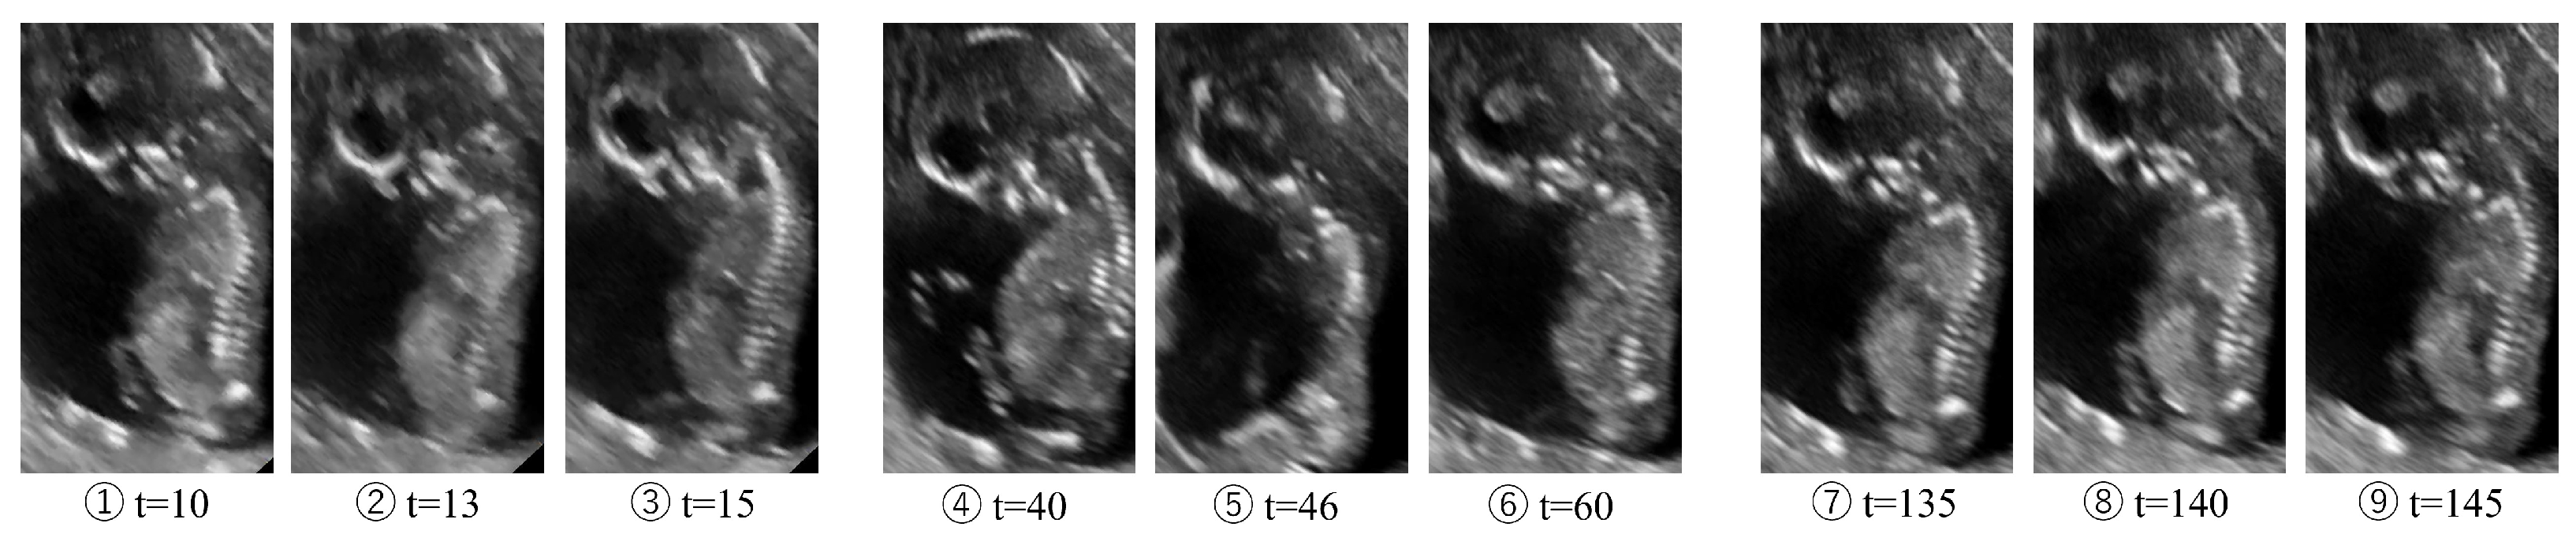

4.4. Application: Intensity of Deformation Estimation